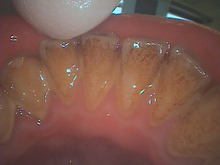

写真は歯石と着色です。

定期的なメンテナンスが必要です。